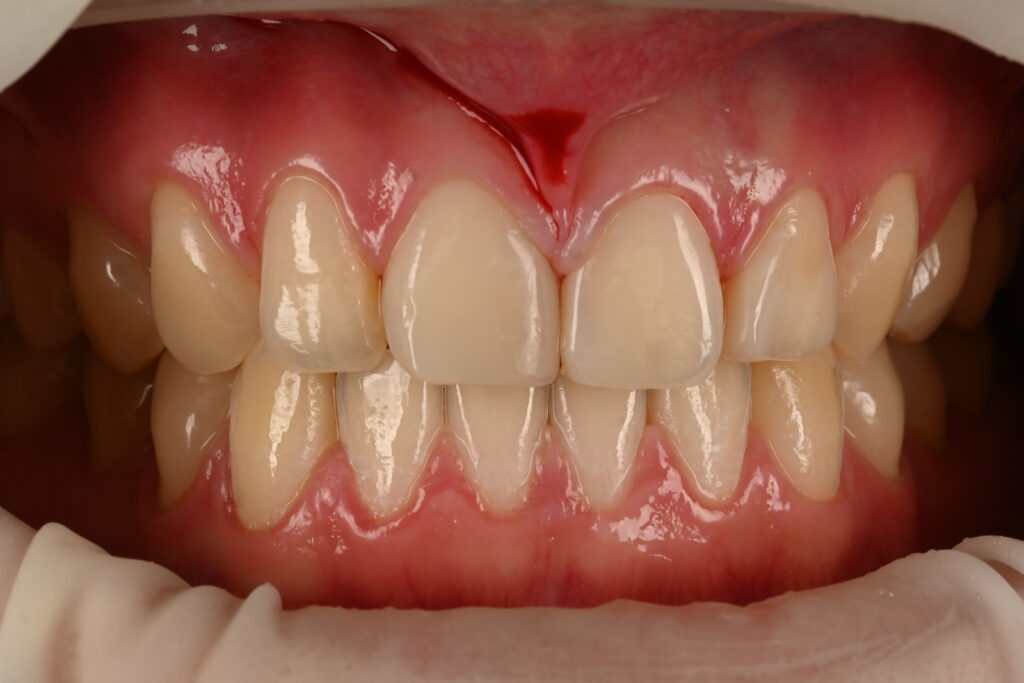

전체적인 앞니 미소가 힘들다고 내원하신경우입니다

양쪽이 동시에 레진이 충전완료 되었습니다

적절하게 치료가 진행이 되고 있는데요

물론 여기서 이상하다고 하는 분들이 있을수도 있지만

지금까지 모양은 절반정도만 완성된 과정입니다

피니싱과 폴리싱을 마친 과정

최종적으로 피니싱과 폴리싱이 완성된 결과입니다

둘 사이에 적절히 채워진걸 확인이 가능하구요